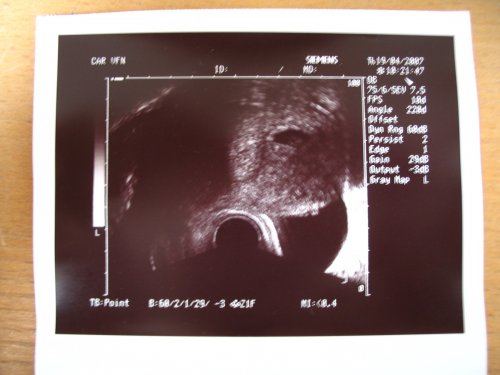

Už se nemůžeme dočkat 1.5....jdeme na 4D UTZ, tak doufám, že se nám ten náš klučík ukáže v plné své kráse 🙂))